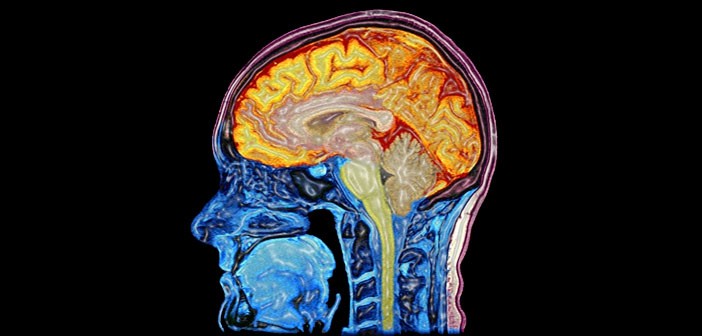

Brain/Head imaging

Conceptual images from various sources